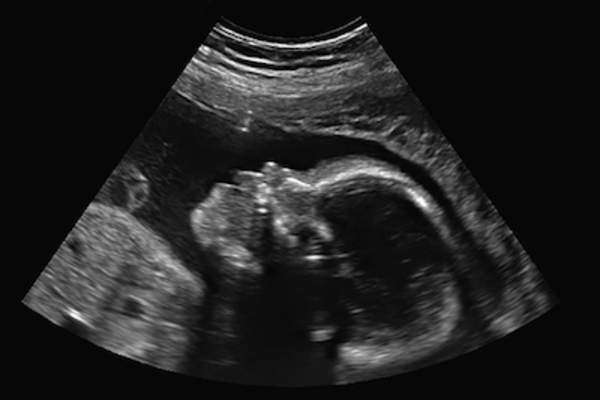

在第三个月,你可能已经开始接受产前护理。你的宝宝有更发达的手,可以在子宫里活动,即使你还感觉不到。手指上甚至还有细小柔软的指甲。你宝宝的皮肤很薄,你可以通过它看到静脉和其他结构。如果你做了超声波检查,你可能还会注意到手臂看起来比腿长——此时宝宝的上半身比下半身发育得更好。